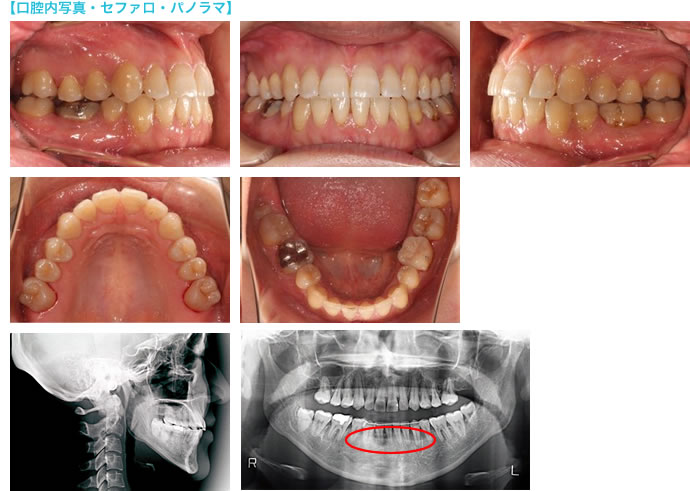

前医で下顎右側第一小臼歯と左側第二小臼歯の合計2本を抜歯し、約2年間のマルチブラケットでの矯正治療が「次回で終わる」と告げられた方が、当院に相談に来られた初診時の口腔内写真です。

下の犬歯が後ろ向きに倒れていて、隙間が残っています。奥歯にはねじれも見られます。この状態で、矯正装置を外して矯正治療を終えると言われたそうです。奥歯に矯正装置がついていませんが、こちらは最初からついていなかったとのことでした。

再治療のための診断・治療計画立案を行うために、レントゲン撮影(セファログラム・パノラマ)、顔面・口腔内写真の撮影、歯型採取等の検査を行い、資料を採取しました。

患者さんのご要望によりお顔の写真をお見せすることはできませんが、再治療開始のセファログラムから、口元(プロファイル)はバランスが取れていることがわかります。

咬み合わせは両側とも、上顎第二小臼歯と下顎第一大臼歯の交叉咬合が残っていました(円で囲んだ部分)。右側は下の犬歯が後ろに倒れており、隙間が残っていました。

パノラマレントゲンで歯の根やあごの状態を確認すると、右下犬歯が歯根吸収していました(丸印部分)。

また、下顎の両側に親知らずを認めました(矢印部分。右側は埋伏していました)。